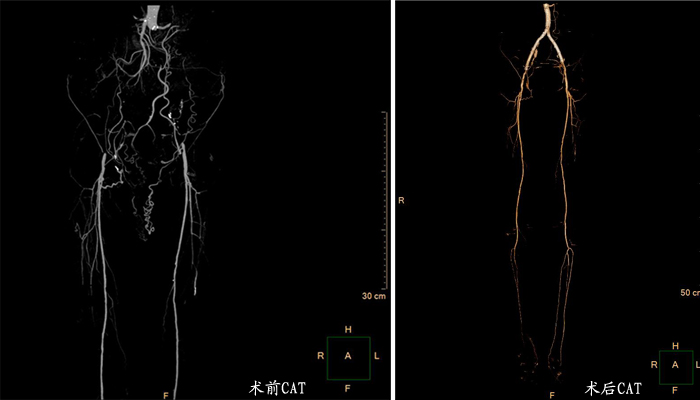

主髂动脉闭塞综合征(Leriche综合征)是指腹主动脉末端及双侧髂动脉完全闭塞的一类疾病,最早是由法国医师Leriche对其进行了系统的临床研究,故以其名字命名。该病征是周围动脉闭塞性疾病中最严重、最复杂的病变,目前,腔内开通技术多在三甲医院的血管外科中心完成。近日,我院普外科疝血管外科专业组成功独立完成了一例Leriche综合征复杂病例。患者张先生67岁,住院时精神状态极差,因缺血性足痛,老人已近一个月夜夜抱着脚不能入睡。经仔细询问,张先生行走后跛行症状已持续一年,既往有10多年高血压病史,得糖尿病也有5年了;有近50年的吸烟史,每天能抽20支。为老人查体时发现其双足及小腿冰凉,皮肤苍白无血色,两侧股动脉触摸不到搏动。血管超声提示:腹主动脉远端、双侧髂动脉闭塞;动脉血管CT造影提示:近肾动脉水平腹主动脉-双髂动脉闭塞。经积极的术前准备,并制定了详尽的手术方案:肱动脉、双侧股动脉穿刺,多入路以确保导丝导管真腔通过;辅以导管溶栓,分步分阶段开通;应用“对吻”技术腹主动脉并行裸支架,双侧髂动脉分别球囊扩张及支架植入。最后,在团队配合下,成功独立完成了完全的腔内开通。术后患者静息痛即消失,三天后能自由下床活动,恢复良好,顺利出院。